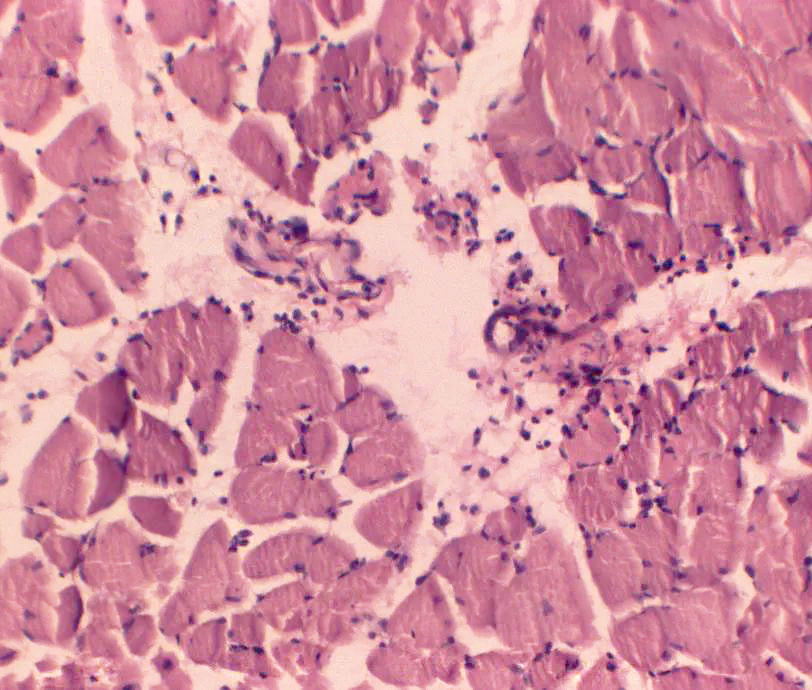

Results and Discussion. All-round analysis of the obtained data revealed that the pathological changes in muscle tissue were aroused in the early period of the postischemic lesions and increased to the end of the 1st day. Histological examination revealed the following changes in the muscle tissue: disorganization of the structural components of the muscle cells, reduction of the striation, friability, fluffiness and rupture of the muscle fibers, violation of their sinuosity, nonlinear arrangement of the nuclei, appearance of the detached necrotic regions and location of the nuclei in the intercellular space. The most significant edema of the muscle tissue occurred on the 1st day in the third group of rats ((41.73±0.39) μm). The average diameter of the muscle fibers in this group was exceeded by 3.37 % the corresponding index ((40.37±0.54) μm) of the control group (P˂0.05). The average area of the nuclei of the muscle fibers ((64.03±0.08) μm) in the third group was only slightly higher than the corresponding value ((63.95±0.07) μm) of the control group (P<0.05). The detected decreasing in the nuclearytoplasmic ratio in the second (0.047±0.001) and the third (0.047±0.001) groups of rats compared with the corresponding indicator of the control group (0.050±0.001) (p˂0.05) may indicate the decreasing in the cellular nuclear activity in the result of ischemic injury.

Conclusions. The results of remodeling of the muscle fibers and the blood vessels of the microcirculatory bed confirm the development of ischemic-reperfusion syndrome in experimental animals. In study of the skeletal muscles of the hind limbs of the white rats after acute ischemia caused by the application of the tourniquet, it was found that the remodeling of the muscle fibers was mainly manifested by edema, homogenization of sarcoplasm, violation of linear arrangement of nuclei in the myocytes and leukocyte infiltration of endoand perimizia, myolysis with the destruction of the sarcolemma and the release of nuclei into the intercellular space. The reactive lesions were developed in the microvessels of all segments and maximally expressed by the end of the 1st day.